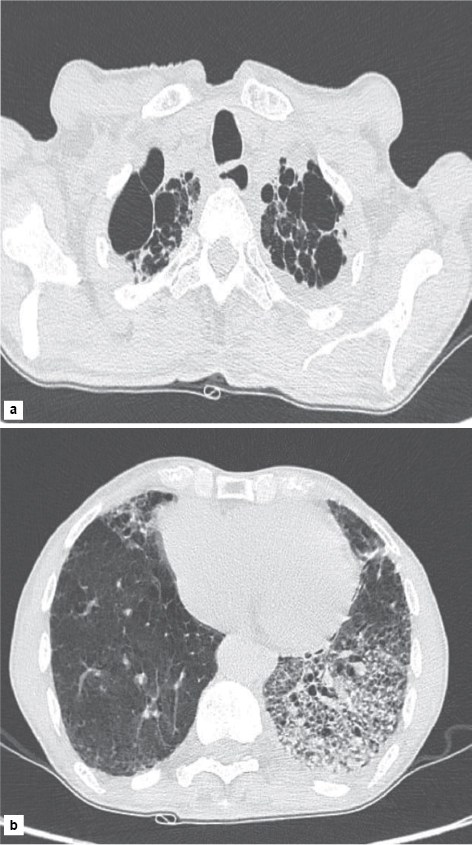

Gram stain and Ziehl-Neelsen (ZN) stain done on induced sputum were negative. The viral markers for human immunodeficiency virus (HIV) and hepatitis B virus (HBV) were negative. High-resolution computed tomography (HRCT) of the chest taken for further evaluation of the patient revealed bilateral apical emphysematous changes with interlobular septal thickening in the left lingula and left lower lobe with consolidation in the left lower lobe with no significant mediastinal lymphadenopathy (Fig. 2).

Figure 2. HRCT of the chest demonstrating (a) bilateral apical emphysematous changes (b) interlobular septal thickening in the left lingula and left lower lobe with consolidation in the left lower lobe.